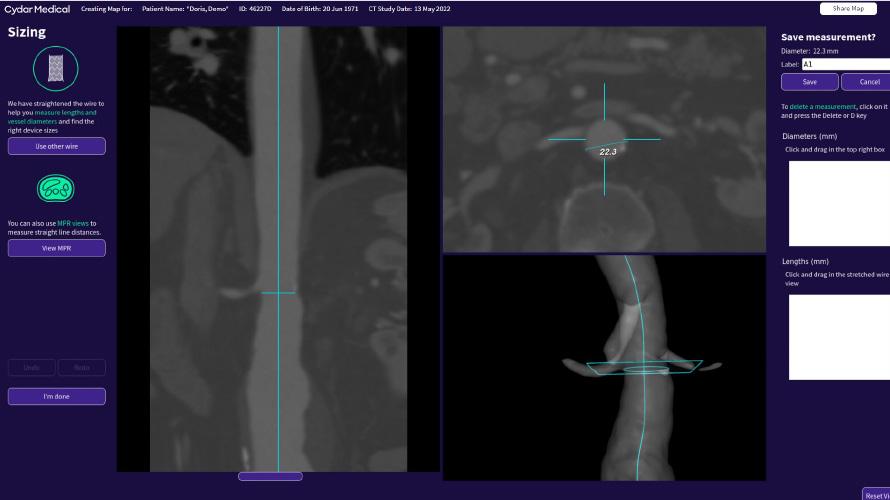

Finally, the presenter gave an overview of the pros and cons of image fusion. He stated that there is one system in this space—the Cydar Medical system—that offers automated registration. This technology compares the anatomy visible on live fluoroscopy with anatomy of a preoperative computed tomography angiography

(CTA) and automatically produces 3D overlay, he explained. According to the presenter, this technology offers “a significant reduction of contrast agent and also reduction of procedure time,” despite having a somewhat “complex setup”. Image fusion is “widely available” and, in the presenter’s opinion, “should be used in all complex procedures”.

During pre-operative planning, Cydar EV Maps processes the CT scan (even if poor quality) to accurately segment the anatomy. This, along with our detailed planning and measurement tools, provides you with the right insights and information at the right time.

Cydar EV Maps automatically adjusts the 3D overlay when changes occur due to C-arm position, patient movement or posture change, minimizing the need for additional registrations.